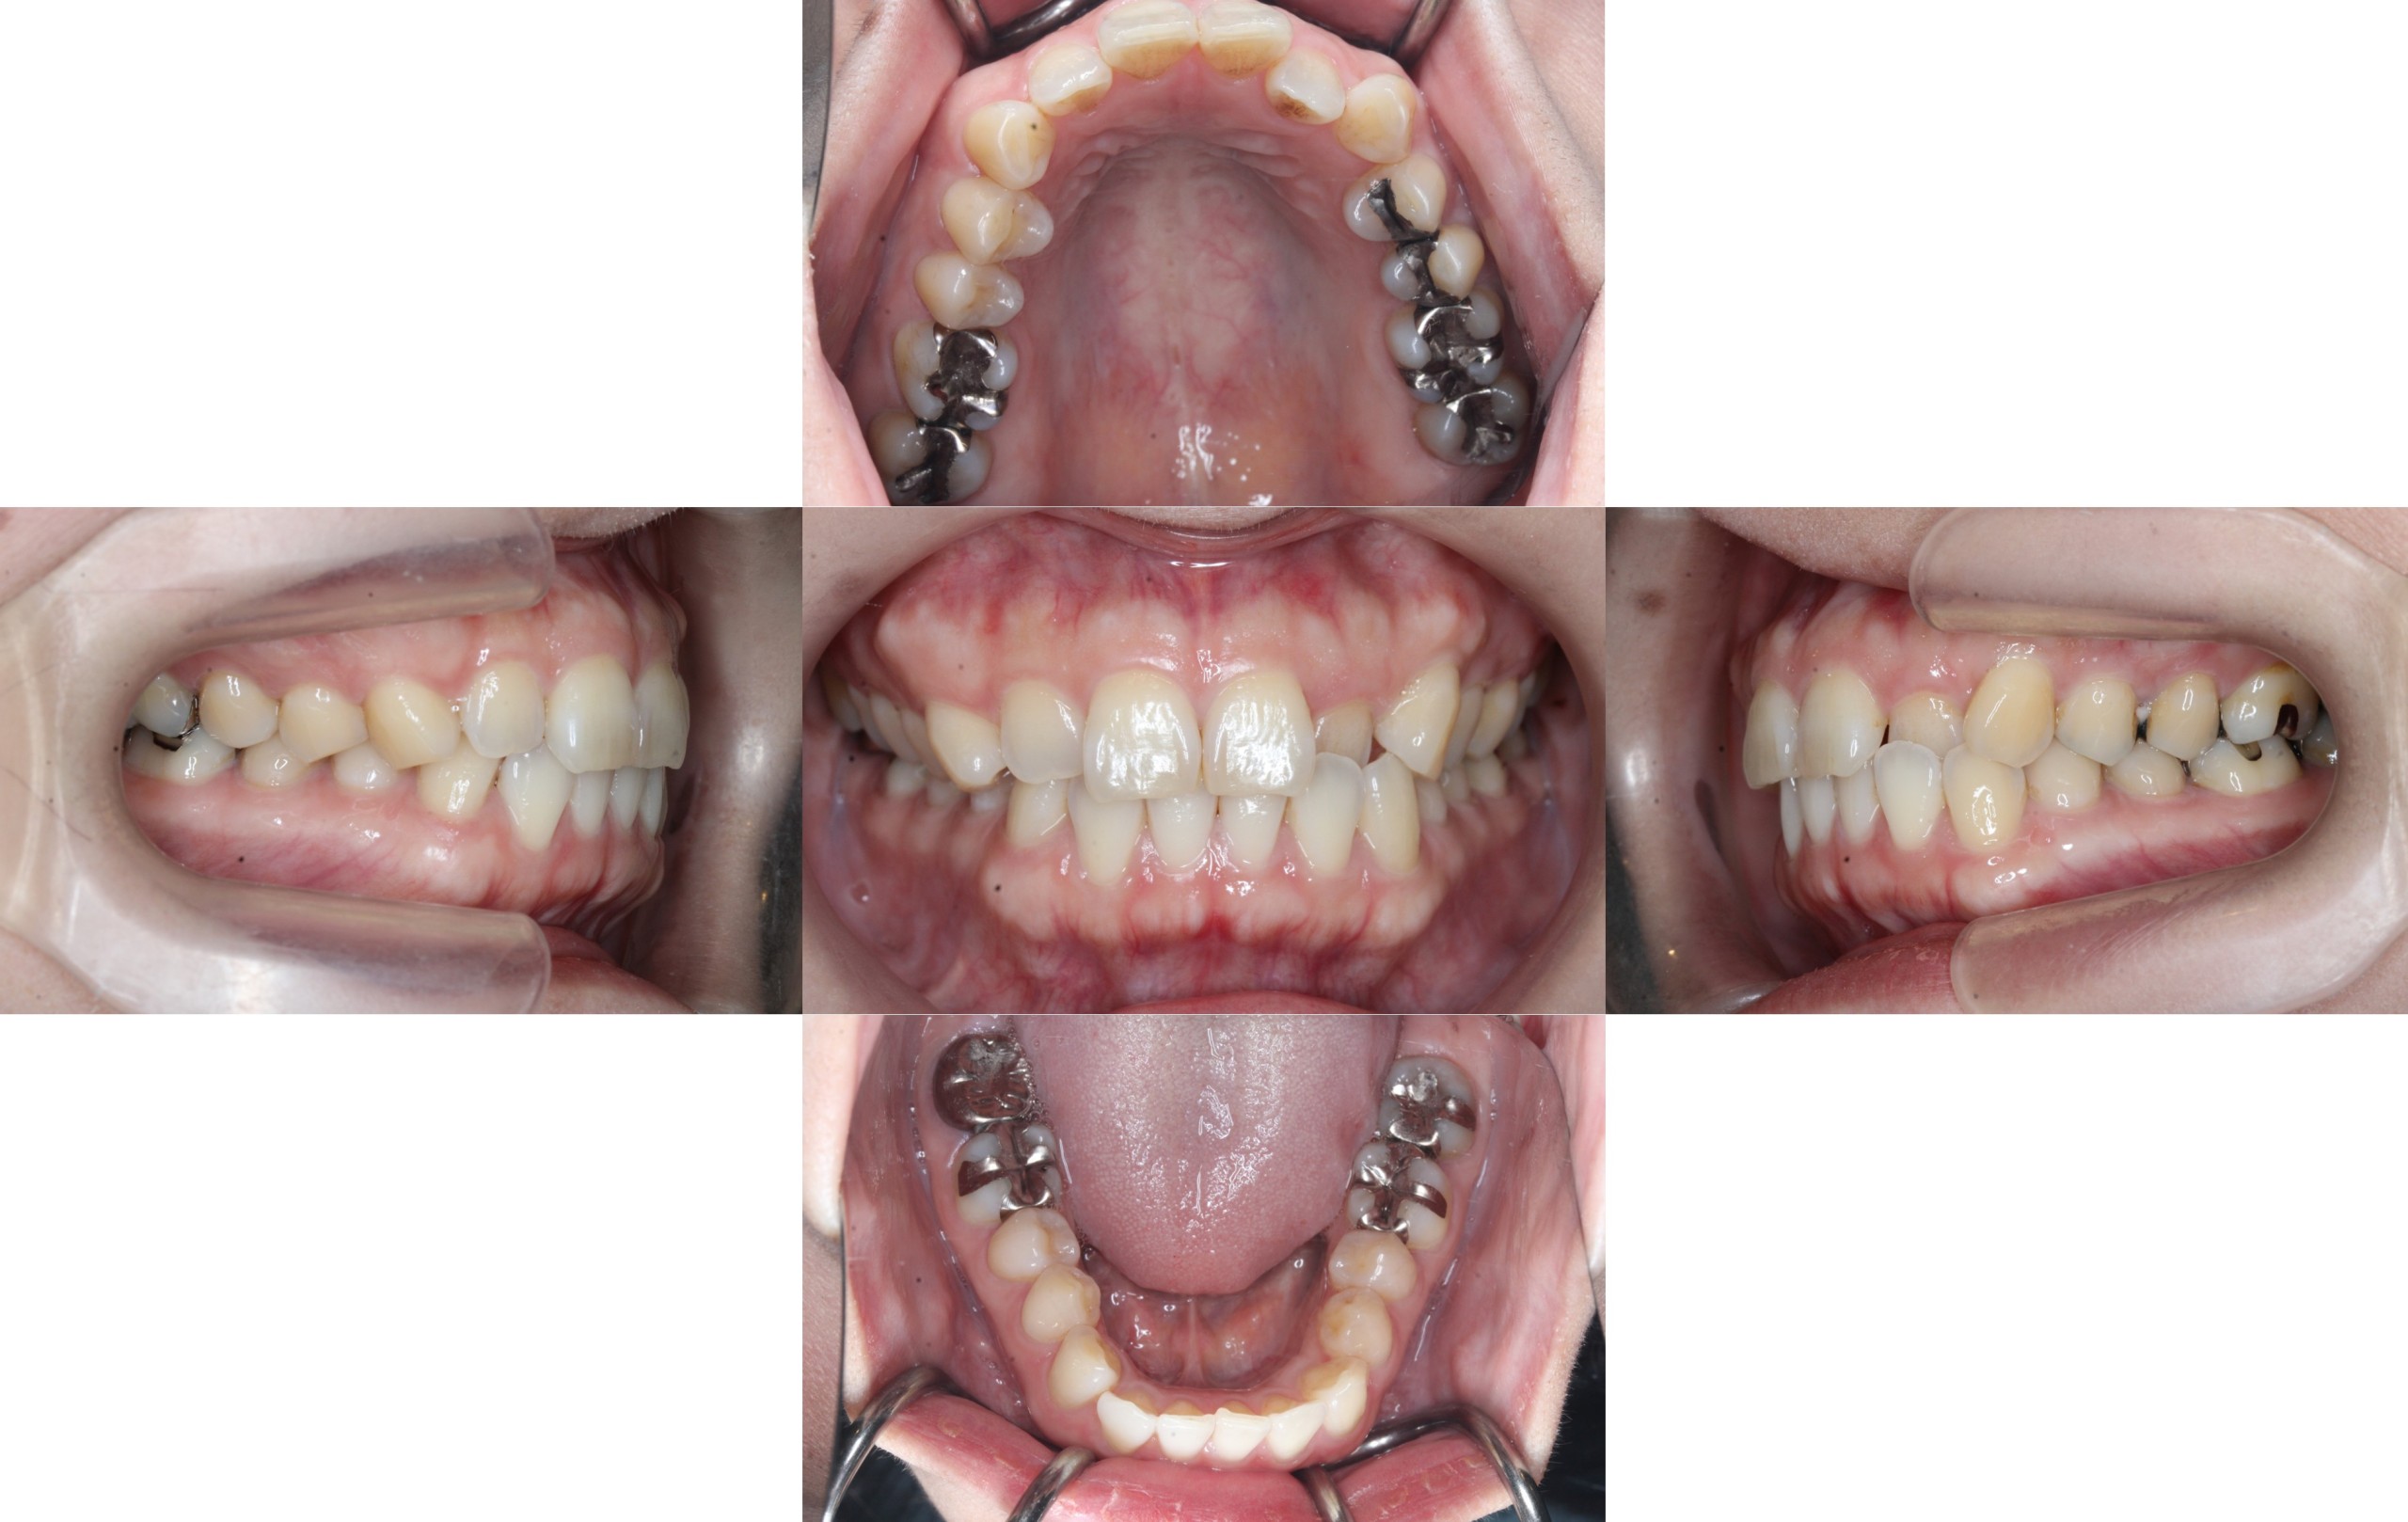

After

約1年2ヶ月経過